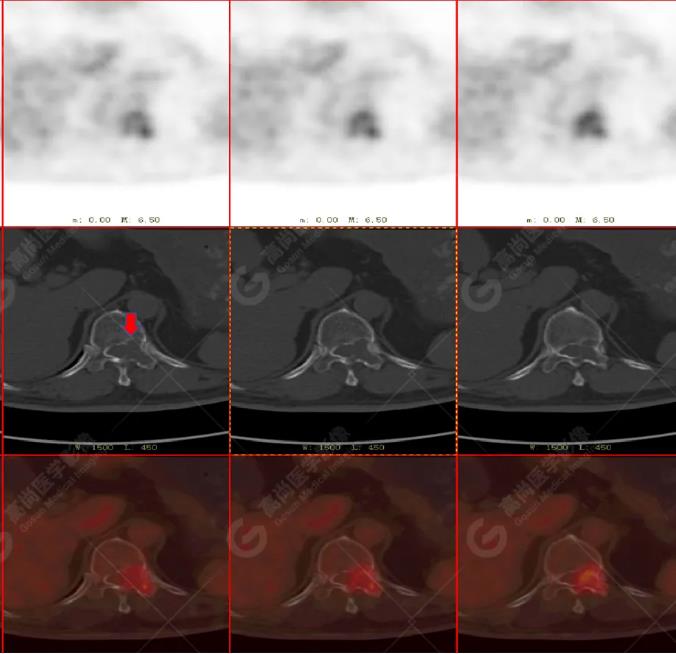

胸椎溶骨性骨質(zhì)破壞,F(xiàn)DG環(huán)狀代謝增高,SUVmax為4.0。

最終診斷:左側(cè)乳腺癌伴胸椎單發(fā)骨轉(zhuǎn)移。